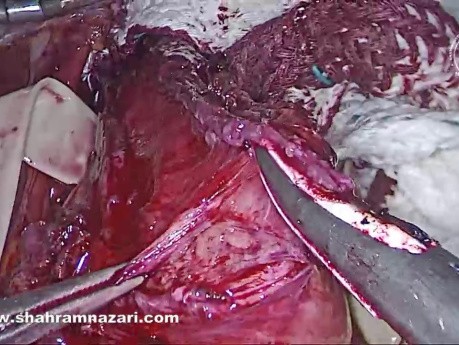

Pose d'un Stent Antérograde du Cholédoque...

L'exploration laparoscopique de la voie biliaire principale (ELVBP) s'est avérée être un traitement sûr, efficace et rentable de la lithiase biliaire. Après ELVBP, la clairance peut être évaluée par cholangiographie...